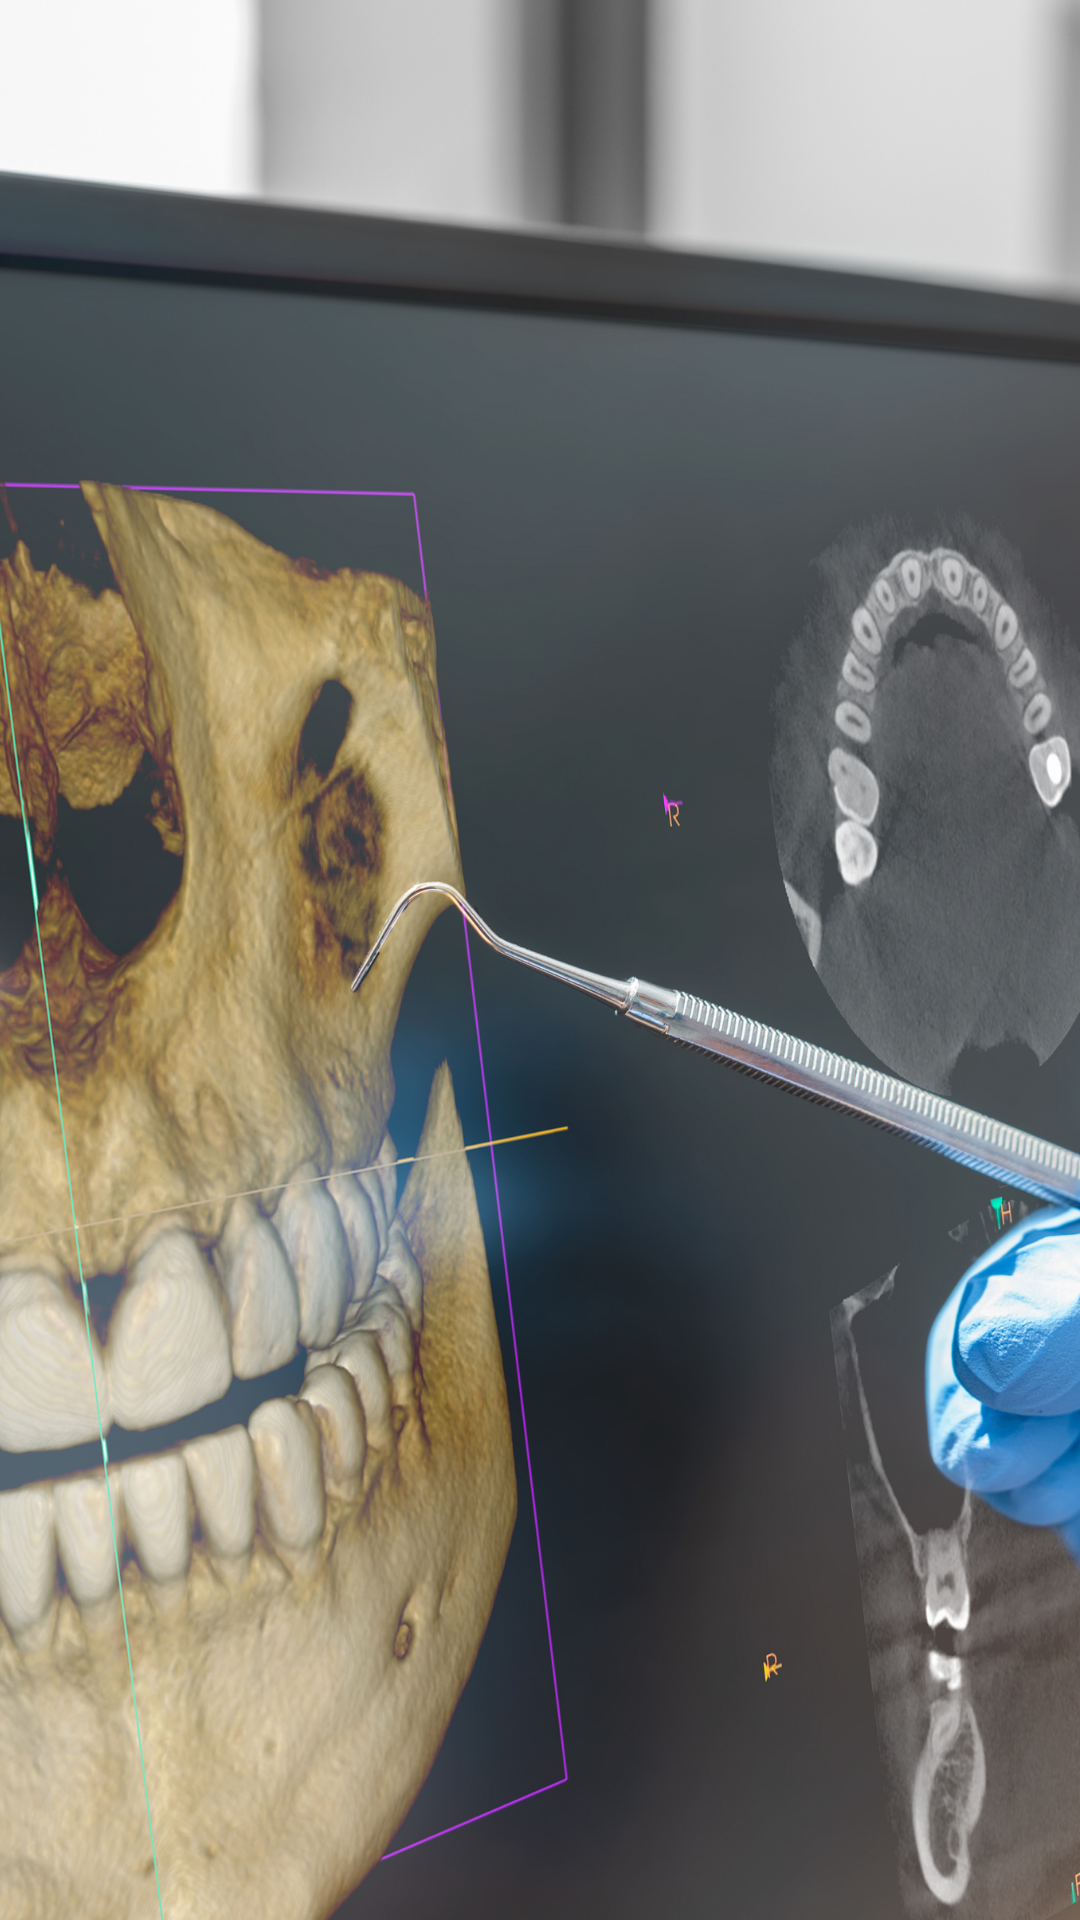

¿Necesitas imágenes tridimensionales precisas? Nuestras tomografías 3D te brindan diagnósticos milimétricos para planificación de tratamientos.

¿Necesitas estudios adicionales? Ofrecemos radiografías especializadas, reportes detallados y análisis de ATM para diagnósticos completos.